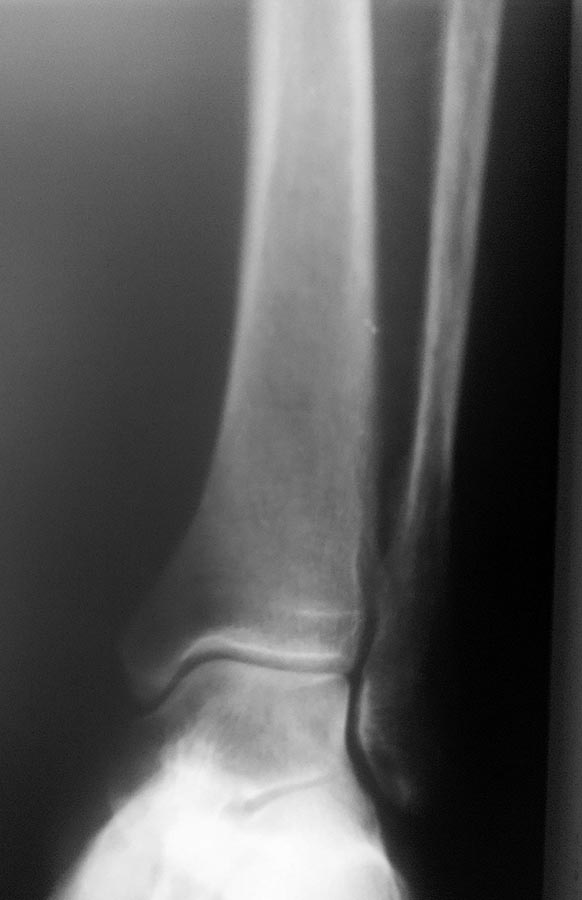

Очевидно, что это перелом не 44С. Механизм травмы - прямой удар. Это косой перелом м/берцовой кости без повреждения голеностопного сустава и межкостный мембраной, которые наблюдаются при переломах 44С. При этом дисторсия связок г/ст сустав возможна как отдельное повреждение, с другим межанизмом, которое последовало вслед за переломом в результате непрямого воздействия. Такой перелом не нуждается ни во внутренней фикции, ни во внешней иммобилизации. Как лечить дисторсию тоже знаете.

Смущает одно, что при наружной ротации стопы боль передаётся на область перелома малоберцовой кости в верхней/3 и болезненность в проекции дельтовидной связки, и линия перелома м/берцовой кости косая (ближе к спирали).

На боковой R-графии ГСС: задний край б/берцовой кости цел.

По рентгенологической картине это перелом от сгибания, а не от скручивания, что бывает при 44С3.